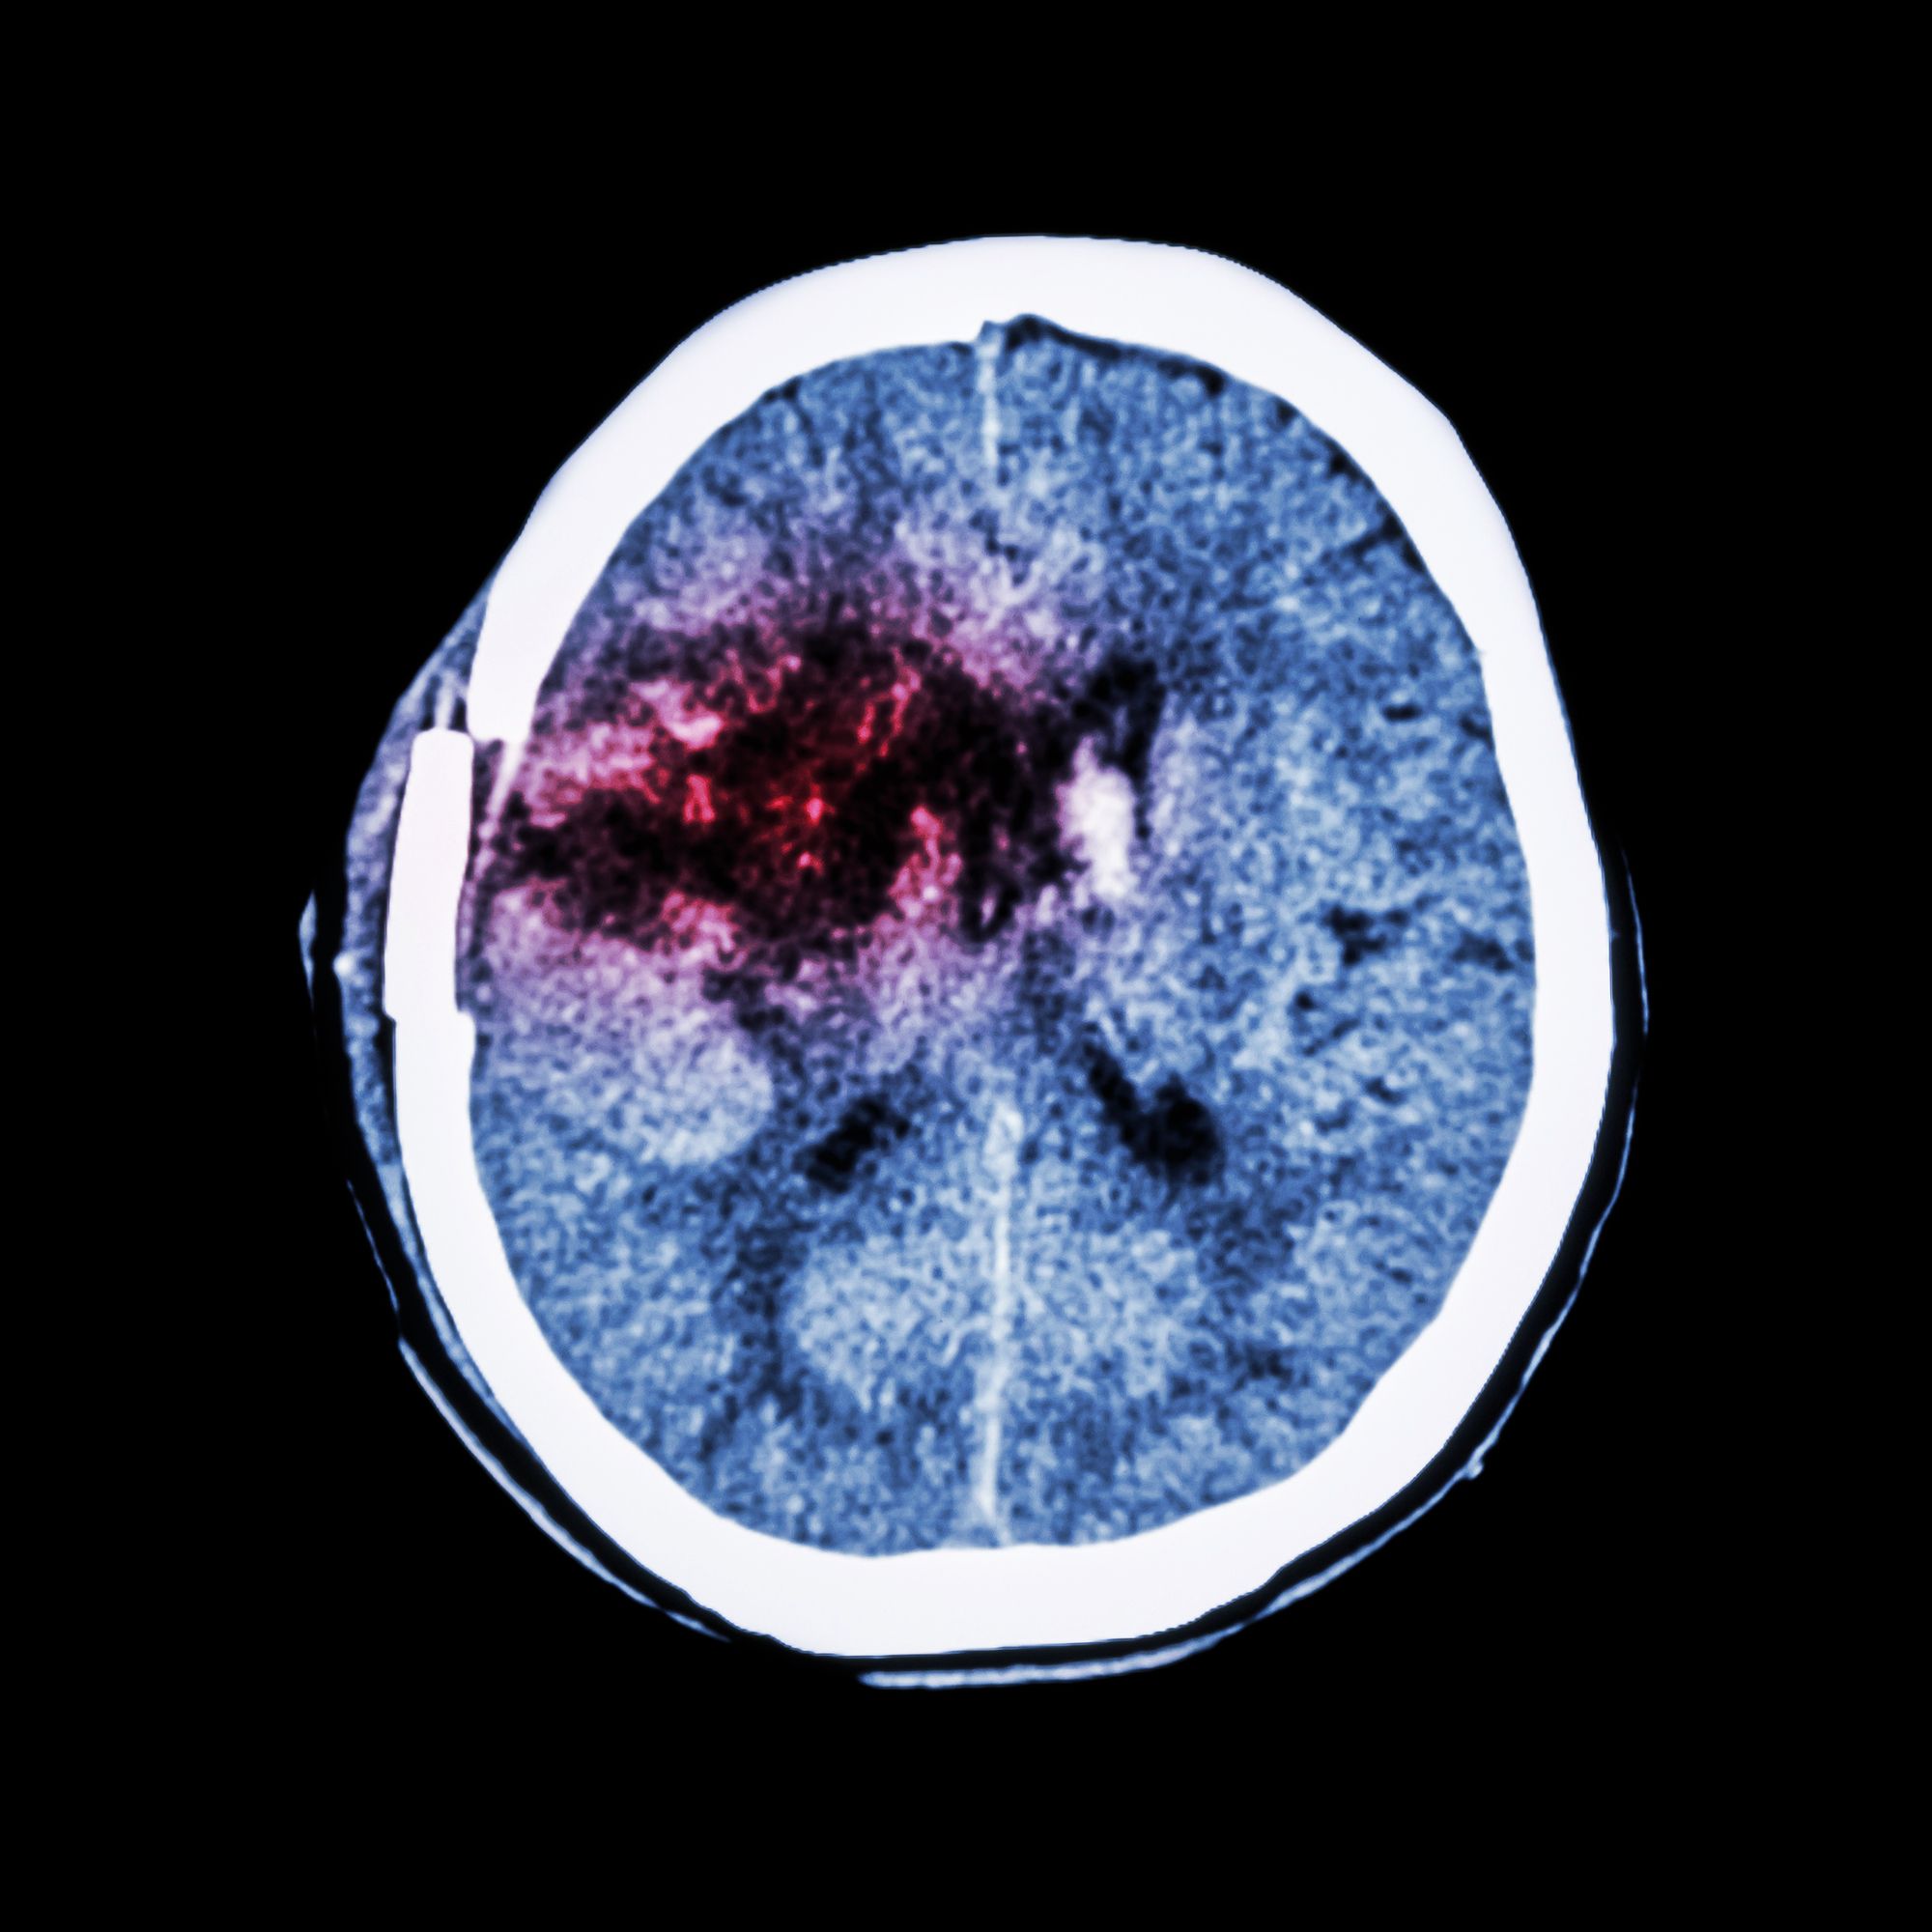

Eliquis Intracranial Hemorrhage Possible Medication Side Effect Blood Thinners Eliquis Side Effects  For example, it might take longer than usual to. This medication can cause serious bleeding if it affects your blood clotting proteins too much. Most of these are related to bleeding, since the drug reduces the blood’s. Most bleeding that occurs with eliquis is mild. Examples include nausea and bleeding. Many people using this medication do not have serious side. Blood Thinners Eliquis Side Effects.